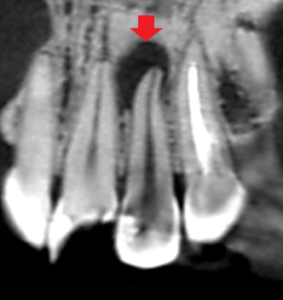

上顎側切歯のレジン充填でむし歯が再発し歯の神経が腐敗した結果、膿ができたと思われるケースです。膿は、唇側から口蓋側にかけて骨が抜けるほどの大きさでした。

上顎側切歯の冠状断のCT画像です。

赤い矢印の先に膿の影が認められます。膿は隣の中切歯の歯根に達しています。